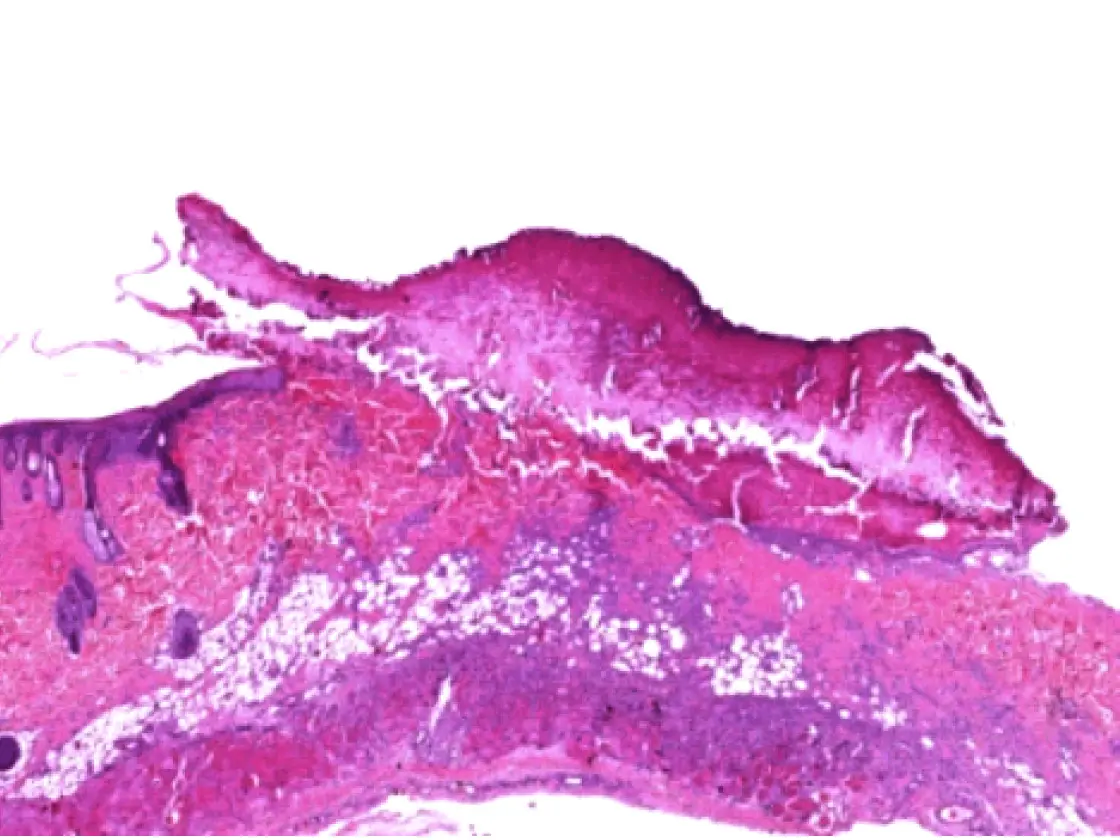

A comparison of the healing process of lesions in albino rats created by different technologies showed proven benefits of the 4 MHz radiofrequency technology in terms of wound healing. Using the impedancecontrolled CURIS© 4 MHz radiofrequency generator turned out to be more targeted and precise compared to conventional high frequency, preserving the basal membrane as well as the deep layers of the epithelium, thus causing less profound wounds.6 The histological assessment also showed that wound healing using the CURIS© 4 MHz radiofrequency generator is faster compared to conventional high frequency. Radiofrequency induced wounds show complete epithelialization after seven days in contrast to the lesions produced by high frequency which show abundant inflammation associated with focal suppurations (see fig. 2).

Histological aspects on day seven: comparing radiofrequency and conventional high frequency

Fig. 2